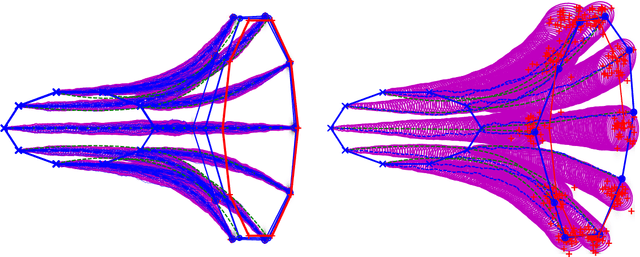

Abstract:Stochastically evolving geometric systems are studied in geometric mechanics for modelling turbulence parts of multi-scale fluid flows and in shape analysis for stochastic evolutions of shapes of e.g. human organs. Recently introduced models involve stochastic differential equations that govern the dynamics of a diffusion process $X$. In applications $X$ is only partially observed at times $0$ and $T>0$. Conditional on these observations, interest lies in inferring parameters in the dynamics of the diffusion and reconstructing the path $(X_t,\, t\in [0,T])$. The latter problem is known as bridge simulation. We develop a general scheme for bridge sampling in the case of finite dimensional systems of shape landmarks and singular solutions in fluid dynamics. This scheme allows for subsequent statistical inference of properties of the fluid flow or the evolution of observed shapes. It covers stochastic landmark models for which no suitable simulation method has been proposed in the literature, that removes restrictions of earlier approaches, improves the handling of the nonlinearity of the configuration space leading to more effective sampling schemes and allows to generalise the common inexact matching scheme to the stochastic setting.

Abstract:We introduce a stochastic model of diffeomorphisms, whose action on a variety of data types descends to stochastic evolution of shapes, images and landmarks. The stochasticity is introduced in the vector field which transports the data in the Large Deformation Diffeomorphic Metric Mapping (LDDMM) framework for shape analysis and image registration. The stochasticity thereby models errors or uncertainties of the flow in following the prescribed deformation velocity. The approach is illustrated in the example of finite dimensional landmark manifolds, whose stochastic evolution is studied both via the Fokker-Planck equation and by numerical simulations. We derive two approaches for inferring parameters of the stochastic model from landmark configurations observed at discrete time points. The first of the two approaches matches moments of the Fokker-Planck equation to sample moments of the data, while the second approach employs an Expectation-Maximisation based algorithm using a Monte Carlo bridge sampling scheme to optimise the data likelihood. We derive and numerically test the ability of the two approaches to infer the spatial correlation length of the underlying noise.

Abstract:We present a framework for shape matching in computational anatomy allowing users control of the degree to which the matching is diffeomorphic. This control is given as a function defined over the image and parameterises the template deformation. By modelling localised template deformation we have a mathematical description of growth only in specified parts of an image. The location can either be specified from prior knowledge of the growth location or learned from data. For simplicity, we consider landmark matching and infer the distribution of a finite dimensional parameterisation of the control via Markov chain Monte Carlo. Preliminary numerical results are shown and future paths of investigation are laid out. Well-posedness of this new problem is studied together with an analysis of the associated geodesic equations.